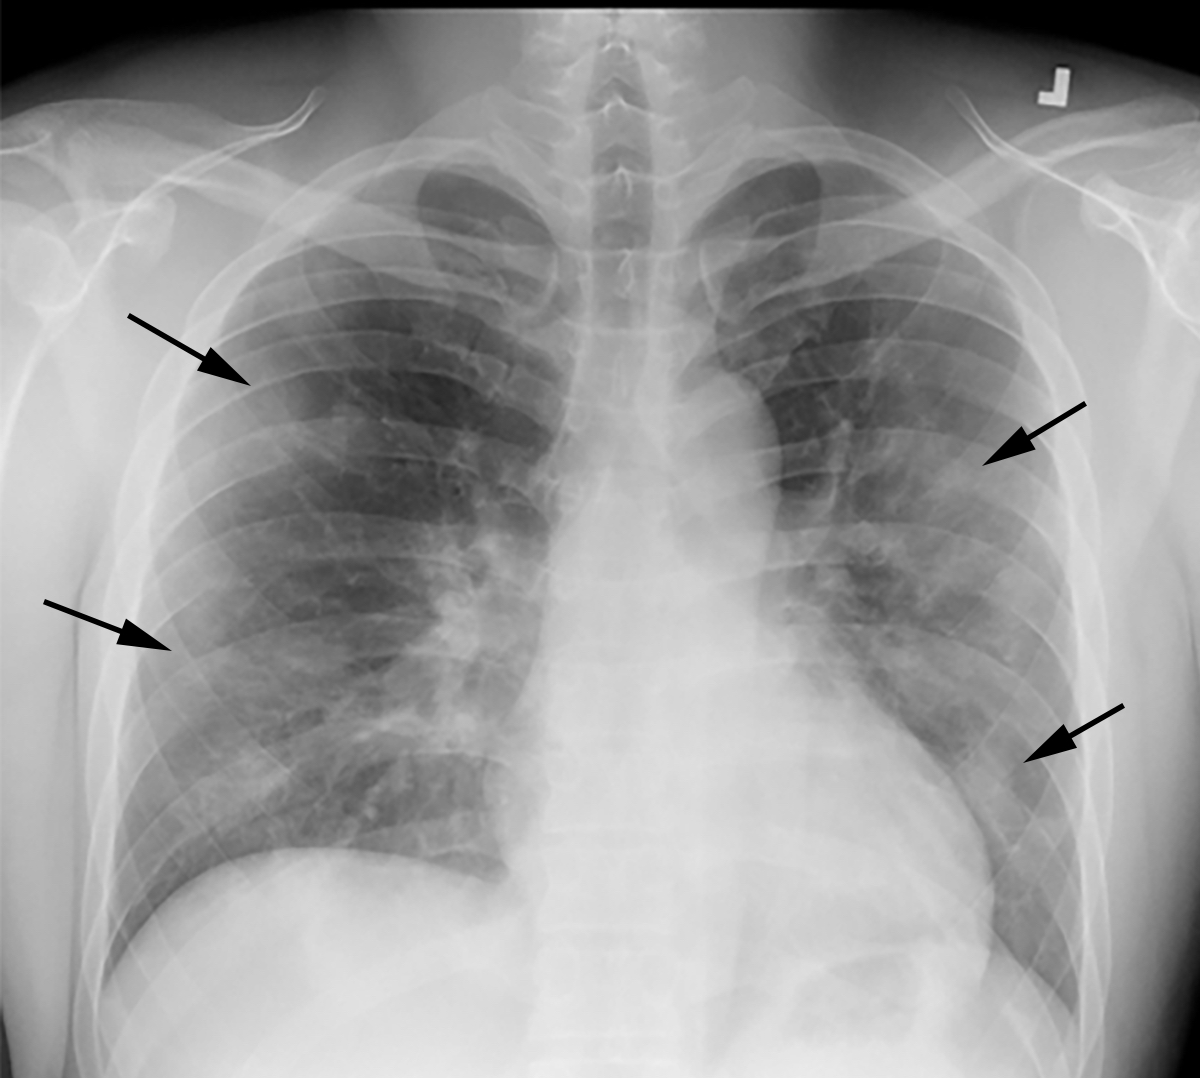

This photo gallery shows the variety of radiological presentations of COVID-19 (SARS-CoV-2) in medical imaging, including computed tomography (CT), radiograph X-rays, ultrasound, echocardiograms and magnetic resonance imaging (MRI). The radiology images show examples of typical COVID pneumonia in the lungs and the numerous complications the virus causes in the body in multiple organs, including the brain, kidneys, heart, abdomen and vascular system.

Ultrasound, especially hand-held ultrasound imaging devices, have become a primary imaging modality for novel coronavirus because of the ease to bag the device and sterilize it after use. CT and mobile X-ray systems are also used as front-line imaging systems for COVID-positive or suspected COVID patients.